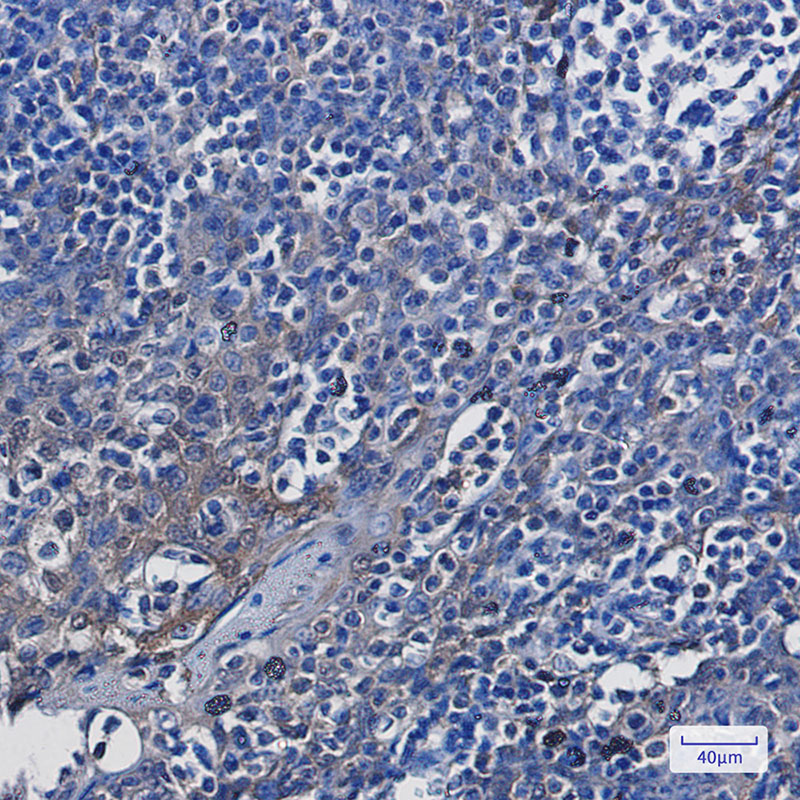

Product Image

- Immunohistochemistry analysis of paraffin-embedded Human tonsil using ENO1 antibody.High-pressure and temperature Sodium Citrate pH 6.0 was used for antigen retrieval.